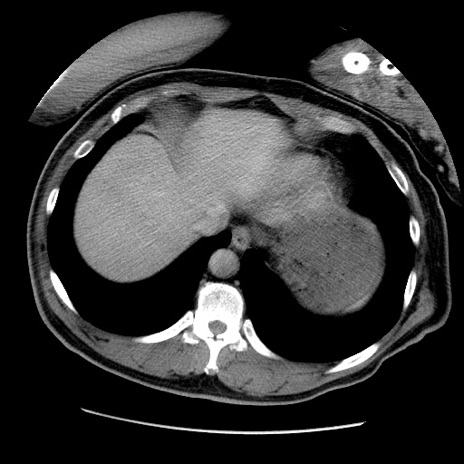

症例22(横断像)

【症例】50歳代男性

【主訴】腹痛

【現病歴】AVMからの被殻出血のため回復期リハ病棟入院中。 本日午後3時頃急に下腹部痛が出現した。

【既往歴】AVM、被殻出血、虫垂炎、高血圧

【身体所見】意識晴明、左半身不全麻痺、会話の理解は良好、36.5°C、腹部:膨隆、全体に板状硬、下腹部正中に圧痛点あり、反跳痛-、筋性防御不明、右下腹部にope scar

【データ】WBC 9400、CRP 0.06